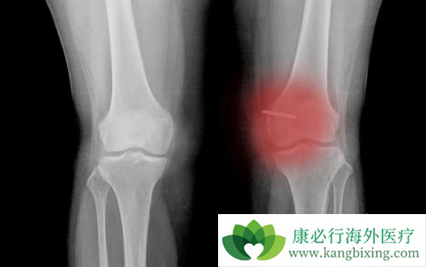

骨纤维肉瘤在骨骼发病部位,类似于骨肉瘤及恶性纤维组织细胞瘤,主要侵及长管状骨,其次为股骨、胫骨、肱骨、腓骨、桡骨、尺骨,膝关节周围骨纤维肉瘤为33%~80%,手及足部小骨少见,骨盆骨发病约为9%,颅骨如果以前无Paget病或未经过放射治疗者,发病极为罕见。